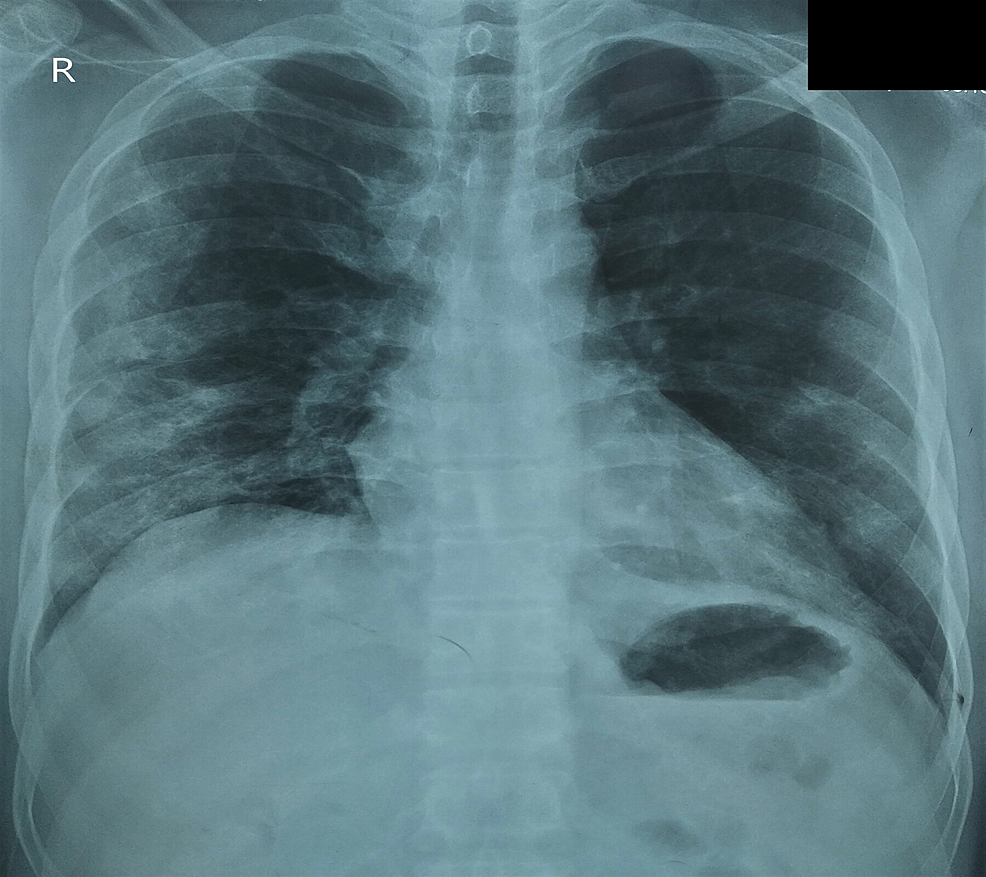

From casereports.bmj.com

Spontaneous pneumomediastinum an important differential in acute chest What Is Spontaneous Pneumomediastinum In the absence of traumatic. This type of pneumomediastinum occurs due to smoking or the use of recreational drugs. Primary or spontaneous pneumomediastinum refers to a form of the condition with no obvious cause. Secondary pneumomediastinum is most often caused by. Spontaneous pneumomediastinum (spm) is a rare entity affecting younger males that is not associated with any possible triggering. Pneumomediastinum. What Is Spontaneous Pneumomediastinum.